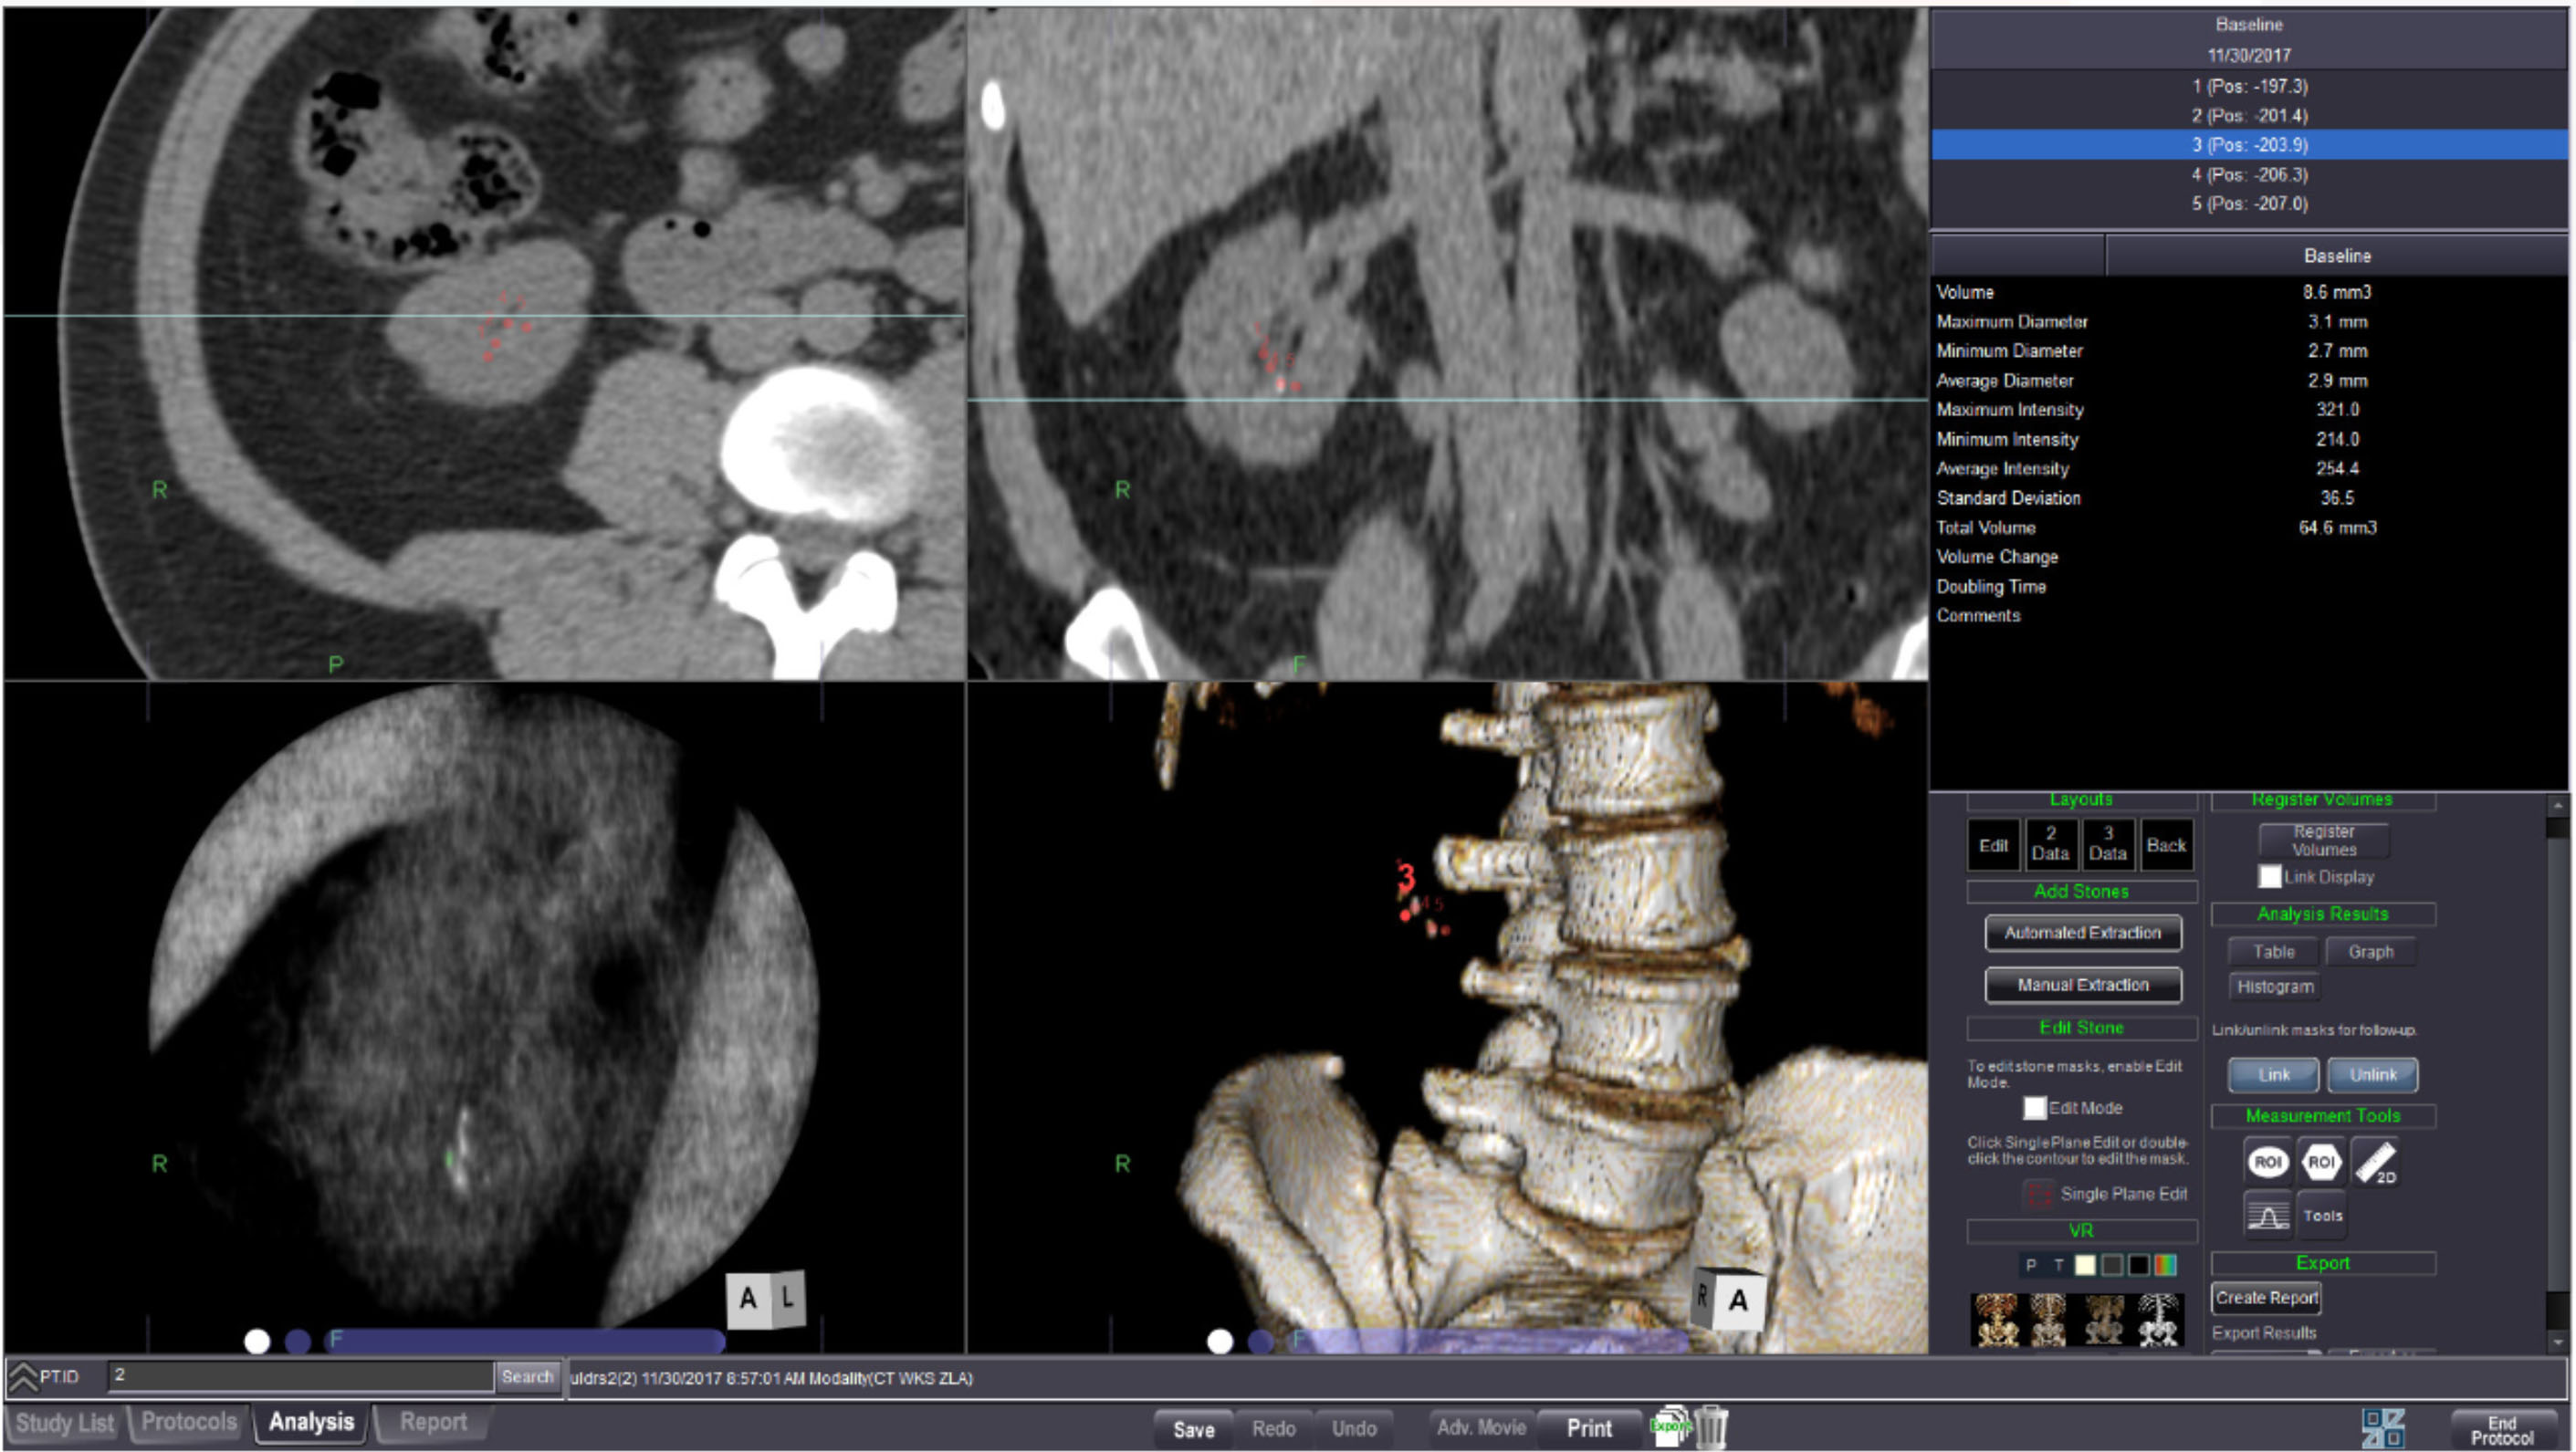

CT RENAL STONE ANALYSIS

A single click stone extraction enables volumetric measurements. This protocol also allows for viewing of baseline and serial exams for comparison.